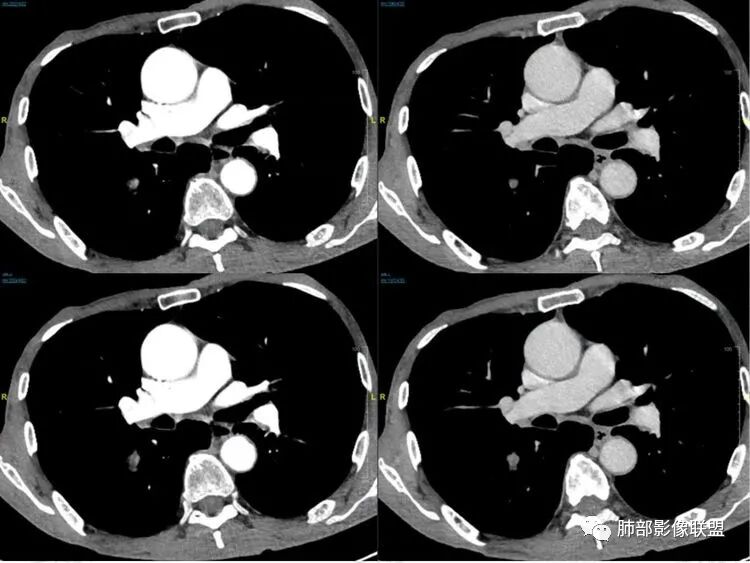

病理结果:小细胞肺癌

关于小细胞肺癌

小细胞肺癌(Small Cell Lung Cancer,SCLC)约占肺癌的15%-30%,起源于支气管粘膜或腺上皮内的Kulchitsky细胞(嗜银细胞),是一种小细胞组成的恶性上皮肿瘤,恶性程度极高、转移早、易复发、预后差、放化疗敏感。

CT主要表现:

1鸭蹼状突起、腊肠样尾巴、指状突起、蠕虫、分支及条状

因为病灶沿支气管粘膜下及周围血管生长,走形方向与支气管一致,所以支气管血管周围生长也是SCLC的典型征象。当然有时会像小山丘或者灌汤包一样趴在肺边缘。

2娘小崽大、淋巴及血行转移早、冰冻纵隔及肺门、血管脂肪间隙消失

因为病灶侵袭力强,病灶易沿淋巴道、间质及心血管间隙等结构侵犯并密切挤压上述结构,常常能够观察到脂肪间隙消失。易于出现冰冻纵隔。原发灶与肺门转移灶可形成哑铃状外观,甚至转移灶体积大于周围原发灶,有人称之为“娘小崽大”。早期病灶有时很小甚或隐匿,仅能看到转移灶,或转移淋巴结与原发灶融合分界不清。病变向肺门延续的串珠样淋巴结转移也是SCLC的典型特点。

3

血管包埋征

病灶侵袭力强大,早期沿粘膜下疏松结缔组织及血管旁间隙扩散,包绕血管,血管会受压变形,因为小细胞癌破坏力弱,血管没有被破坏,所以仅仅表现为包埋浸润,但血流面光滑。

4

乏血供,沼泽样坏死

、罕见空洞

病灶肿瘤密集而供血血管相对不多,密度较均匀,轻度强化,呈乏血供,有时候可以坏死,坏死不彻底,坏死区分散而较小,呈沼泽样坏死,很难造成引流支气管的破坏,所以空洞罕见。

5

阻塞性炎症轻,阻塞性肺不张少见

支气管内肿瘤大多来自淋巴结转移,而且侵入支气管管壁的SCLC组织喜欢沿粘膜下组织间隙浸润,支气管粘膜面保留,所以支气管大多数表现为狭长而非填塞或截断,所以阻塞性炎症轻,阻塞性肺不张罕见。

6边缘圆钝、光整,未见毛刺

神经内分泌肿瘤边缘通常圆钝,而且SCLC或周围没有任何促纤维结缔组织反应,质地软,所以边缘圆钝、没有毛刺。